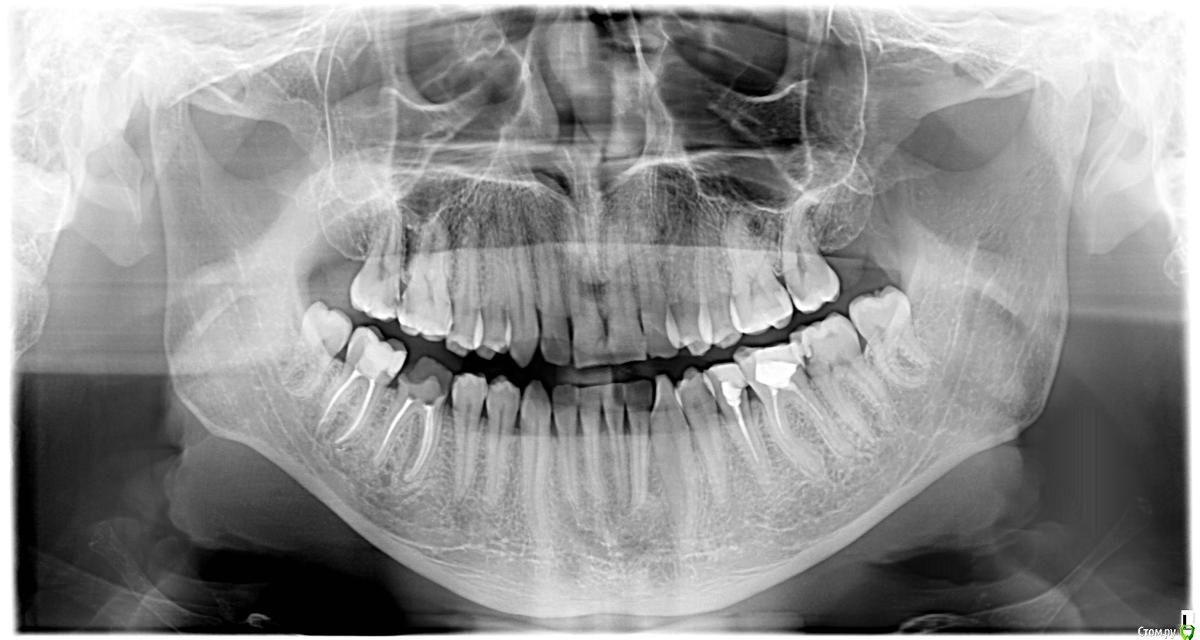

ARislanV Опубликовано 28 мая, 2015 Поделиться Опубликовано 28 мая, 2015 Приветствую всех, Здравствуйте, Начинаем!Пол года назад лечил 36Pt зуб, коронковая часть разрушена на 70 %, восстановил все композитом с перекрытием бугров.Сейчас зуб треснул, по словам удалявшего хирурга трещина до бифуркации. Почему он раскололся? Ведь что интересно, трещина прошла не по краю зуб/пломба ( в самом слабом месте), а посередине пломбы т.е. пломба разорвалась по палам. А какая сила должна была быть, что бы разорвать пломбу по полам?) И следующий вопрос, что делать и как делать, чтобы такого не было? ( потому что мне было очень не приятно видеть такое со своей работой) Ссылка на комментарий

red_butler Опубликовано 28 мая, 2015 Поделиться Опубликовано 28 мая, 2015 Почему он раскололся?Необоснованно расширили показания для реставрации И следующий вопрос, что делать и как делать, чтобы такого не было?протезировать такие зубыP.s. седьмой зуб может повторить судьбу шестого 3 Ссылка на комментарий

ARislanV Опубликовано 28 мая, 2015 Автор Поделиться Опубликовано 28 мая, 2015 Этот зуб был разрушен на 70%, конечно его нельзя было восстанавливать пломбой.) Это моя ошибка, из за которой доверие пац ко мне сильно снизилось. Но я не могу понять, при каких случаях надо: - Делать вкладку и коронку- Пломбу и коронку- Вкладку керамическуюОбъясните пожалуйста?) Ссылка на комментарий

M@estro Опубликовано 28 мая, 2015 Поделиться Опубликовано 28 мая, 2015 Этот зуб был разрушен на 70%, конечно его нельзя было восстанавливать пломбой.) Это моя ошибка, из за которой доверие пац ко мне сильно снизилось. Но я не могу понять, при каких случаях надо: - Делать вкладку и коронку- Пломбу и коронку- Вкладку керамическую Объясните пожалуйста?) пломба - 30 процентов разрушения по площади, витальный зуб. Полость мод , отсутие хотя бы двух стенок - вкладка . Депульпированный зуб . если отсутсвует две стенки и площадь разрушения не более 50 % ( первичный пульпит МОЛЯРА ) - вкладка / накладка. С премолярами сложнее , если стенки более 1.5 мм толщиной - можно сделать коронку 3/4 , в остальных случаях - коронка. Если имеем мод полость у моляра, и зуб депульпирован - то это коронка. Ссылка на комментарий

ARislanV Опубликовано 31 мая, 2015 Автор Поделиться Опубликовано 31 мая, 2015 Как я понял, если зуб живой:разрушен до 30% - то пломбаразрушен более 30% - накладка ( керамическая или композитная) депульпированный зуб:разрушен до 50% - накладкаесли более 50% - то вкладки и коронка Так M@estro ? ) 2 Ссылка на комментарий

Чертков Александр Опубликовано 31 мая, 2015 Поделиться Опубликовано 31 мая, 2015 (изменено) Я бы внес небольшую поправку...депульпирован - коронован! 3/4 или полная коронка...ну или винир 360 градусов Изменено 31 мая, 2015 пользователем Чертков Александр 1 Ссылка на комментарий